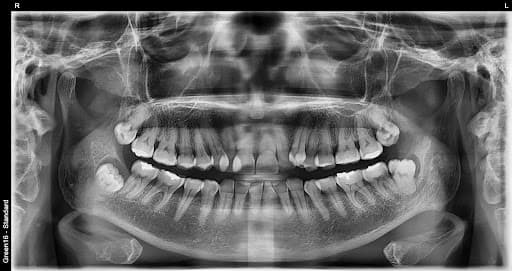

After

O'rta xavf

Qisman ko'milgan aql tishi

Ovqat qoldiqlari yig'ilib qolishi oson va yallig'lanish tez-tez yuzaga keladi

Yotgan aql tishi

Yon tomonga qarab o'sadi va qo'shni tishni bosishi mumkin